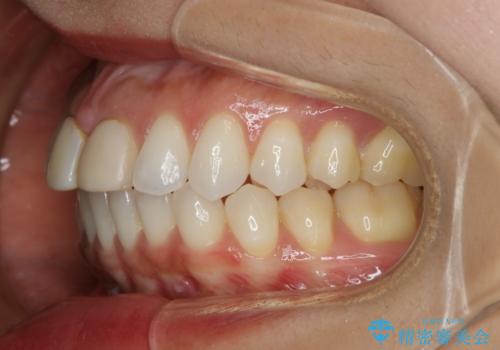

すきっ歯を治したい。インビザライン・ライトによる矯正治療

- 正中離開を気にされて来院された患者様です。

インビザラインでの治療を希望され、正中離開のみ治したいとのことだったので、インビザライン・ライト(片顎)での治療を選択しました。

インビザライン・ライトは枚数が少ないため歯の移動量に限界がありますが、短期間での治療が可能です。